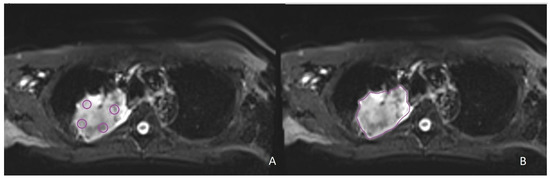

3.2. Correlation of ADC, D, D*, and pf Values with PD-L1 Expression in NSCLC